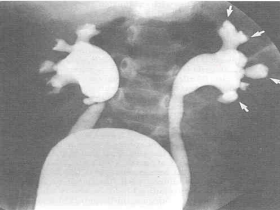

(三)影像学检查

2. X线检查 排尿性膀胱尿道造影3.核素检查 99mTcDMSA 肾瘢痕较敏感肾动态显像

▪ VCUG – f UTI